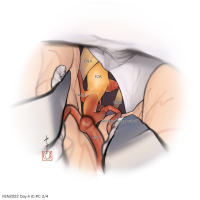

FEN2022シリーズ